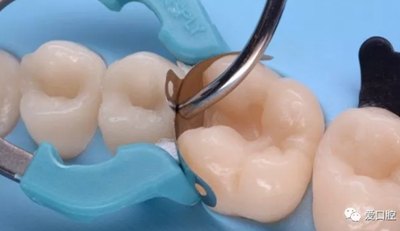

2. 接觸區(qū)恢復(fù)不良

( 1 )原因

充填體與鄰牙的鄰接區(qū),在形狀、位置、大小和牙間楔狀隙的形態(tài)上存在異常。如:無接觸或接觸點面積過大、過小、充填體邊緣嵴與鄰牙邊緣嵴高度不一致,鄰牙邊緣嵴缺損等。

( 2 )臨床表現(xiàn)

患牙區(qū)食物嵌塞,牙齦乳頭紅腫或萎縮。

( 3 )處理

磨改鄰面充填體形態(tài);磨改鄰牙;去除舊充填體,使用鄰面解剖式成型系統(tǒng)重新充填;嵌體、高嵌體、冠修復(fù)。